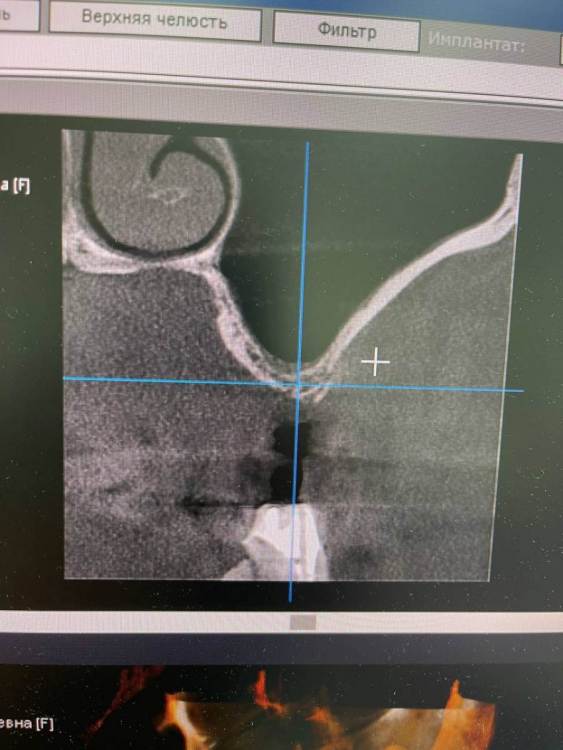

TIGER Опубликовано 8 мая, 2023 Автор Поделиться Опубликовано 8 мая, 2023 Всем привет!планировал удаление,но во время синуса решил использовать фрагмент как клин для стабилизации болта,в итоге совершил ошибку с более медиальной позицией 26,ибо шаблон не изготовил....через 5 мес одел времяхи,т.к будет тотал Ссылка на комментарий